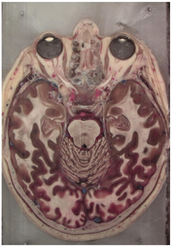

Table 2, Table 3, Table 4 and Table 5 present the results obtained through the multi-objective optimization image enhancement approach. Specifically, Table 2 and Table 3 show the results for natural images, while Table 4 and Table 5 display medical images. The tables are organized as follows: the first and second columns list the image names and their corresponding original, unenhanced versions. The third to fifth columns showcase the selected points from the Pareto front, representing the maximum contrast, knee point, and maximum detail, in that order. The final column illustrates the obtained Pareto front through the optimization process, with red, green, and orange points indicating the images that achieved maximum contrast, knee point, and maximum detail, respectively.

Table 4.

Medical image results—1.

As observed in the results, the images extracted from the Pareto front significantly maximize contrast and detail compared to the original images. In all study cases, the original image is dominated by the solutions extracted from the fronts, demonstrating the approach’s effectiveness in improving visual quality. However, the differences among the three enhanced images for each problem require a more detailed analysis.

For medical images, there are instances where differences are more perceptible. For example, in the Medical3 image, the maximum contrast solution makes it difficult to visualize the internal details of the basophil (a white blood cell highlighted in the box), which could result in a less accurate interpretation. In contrast, the knee and maximum detail solutions provide a clearer view of the interior of the white blood cell. Similarly, in the Medical5 image, the maximum contrast solution highlights the hand and arm bone structures. However, the maximum detail image offers a more precise view of the internal structures within the bones (see the highlighted region), which is crucial for a more detailed evaluation. Another notable example is the Medical8 image, where the maximum detail solution offers a more detailed view of the internal structure of the eosinophil (another type of white blood cell). However, the maximum contrast image improves the visibility of red blood cells. As shown in the yellow box, this solution reveals a red blood cell that is nearly imperceptible in the other solutions. An interesting case is the Medical6 image, where only a few non-dominated solutions are present on the Pareto front. Despite the similarities among the preferred solutions, the nodules are much more perceptible in the enhanced images than in the original image, as observed in the highlighted region.